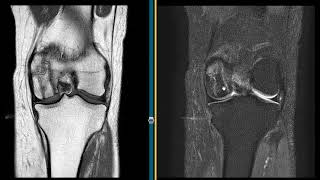

Osteonecrosis Of The Knee

916

2:28

What Wrong With This Knee

4.5 K